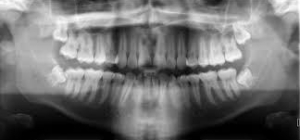

Ortopantomografia digitale: è una vera e propria immagine bidimensionale della bocca che permette di studiare le due arcate dentali, l’osso mandibolare e mascellare, le articolazioni e i tessuti gengivali. I vantaggi dell’OPT digitale sono la bassa emissioni di radiazioni e la possibilità di avere immediatamente l’immagine disponibile. L’OPT digitale consente la valutazione complessiva delle strutture ossee e dentali con valutazioni specifiche nell’ambito di vari settori specialistici.

Consente la visualizzazione di:

- Aree osteolitiche/osteoaddensanti eventualmente da chiarire con ulteriori esami (TAC, risonanza);

- Alterazioni anatomiche dei condili mandibolari;

- Riassorbimento osseo di tipo orizzontale/verticale con eventuale presenza di tasche ossee angolari;

- Processi cariosi e granulomi periapicali;

- Disponibilità ossea a scopo implantare.